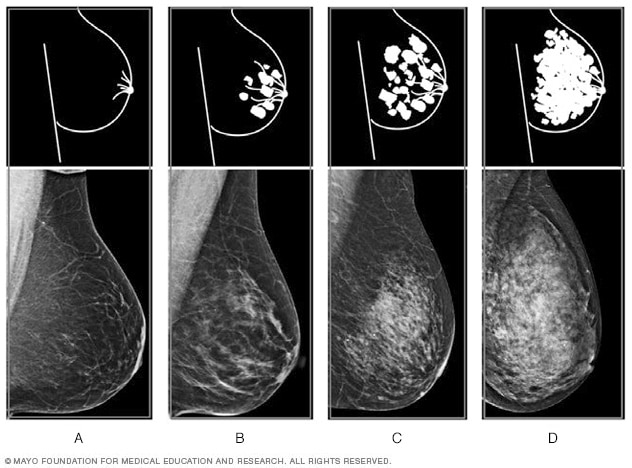

Densidad mamaria: los cuatro niveles

Los resultados de la mamografía a menudo incluyen información sobre la densidad mamaria. Los profesionales de atención médica utilizan el Sistema de informes y registro de datos de estudios por imágenes de la mama para conocer la densidad mamaria. Según este sistema, los niveles de densidad (de izquierda a derecha) se describen de la siguiente manera: A) predominantemente graso, B) zonas dispersas de densidad fibroglandular, C) heterogéneamente denso y D) extremadamente denso.

- A: Predominantemente graso significa que el tejido de las mamas está compuesto por grasa casi en su totalidad. Hay muy poco tejido mamario denso.

- B: Zonas dispersas de densidad fibroglandular significa que las mamas están compuestas en su mayoría por tejido graso. Pero hay algunas áreas dispersas de tejido mamario denso.

- C: Heterogéneamente denso significa que la mayor parte del tejido mamario es denso. Pero hay algunas áreas de tejido graso.

- D: Extremadamente denso significa que casi todo el tejido mamario es denso. Hay muy poco tejido graso.

En general, se considera que tiene mamas densas si el informe de la mamografía dice que tiene mamas con densidad heterogénea o extremadamente densas. Alrededor de la mitad de las personas que se realizan una mamografía tienen mamas densas.